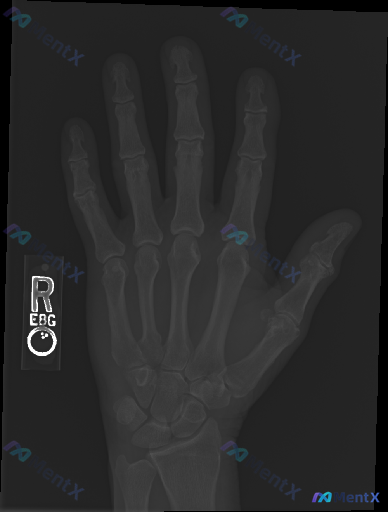

整理到一个值得讨论的影像相关情况: 病例背景 一份右手正位X光片,常规影像学评估结果如下: - 各指骨、掌骨、腕骨骨皮质连续性未见明显中断,无明确骨折线、隐匿性骨折征象或骨膜反应; - 各掌指、指间关节及腕骨间关节间隙基本正常,对位良好,无脱位半脱位; - 骨质密度分布均匀,未见明显骨质疏松、骨质硬...